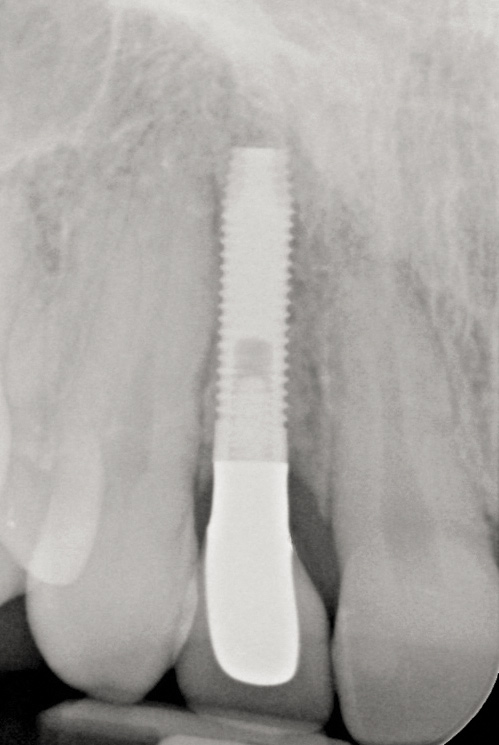

Fig 13. The final radiograph of the seated crown showing a healthy bone level around the implant.

Figure 13

Fig 17. Radiograph showed symmetrical infrabony defect affecting 50% of the implant surface.

Figure 17